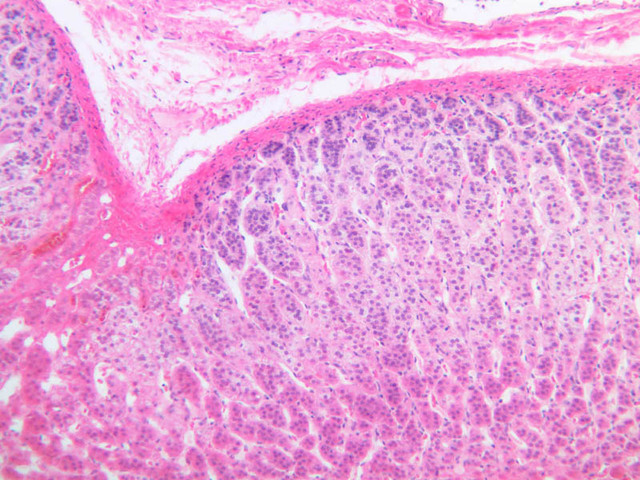

Examine slide B-56 (H&E [2.5x, 10x, 20x, 40x-labeled] [10x, 20x, 40x-labeled] [20x, 40x] [10x, 20x, 40x-labeled] [10x, 20x, 40x]). The connective tissue capsule of each parathyroid gland is continuous with that of the thyroid gland. It extends into the substance of the gland, dividing it into poorly defined lobules. Fat cells may separate the groups of cells and increase with age. Note the rich capillary network. The parenchyma is composed of two types of cells: (1) Principal or chief cells and (2) oxyphil cells. The polygonal chief cell is by far the more numerous cell type. Its nucleus is centrally located and has a vesicular chromatin pattern with a prominent nucleolus and its cytoplasm stains rather lightly. Oxyphil cells, which are less regular in shape and considerably larger than chief cells, are scattered singly or in small clusters. Their nuclei are smaller and more condensed than those of the chief cells and, owing to a very rich complement of mitochondria, their cytoplasm is distinctly acidophilic.